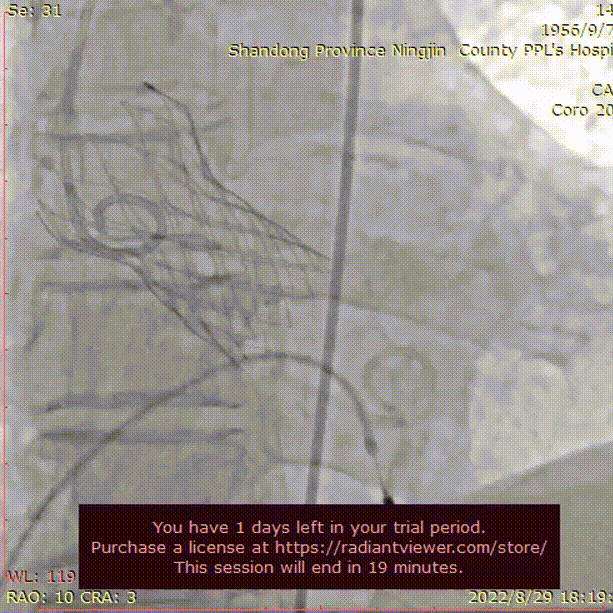

行冠脉造影,LM末端50%狭窄,PDA近中段50-60%狭窄,中段90%狭窄,LCX近中段60-70%狭窄,RCA全程50-70%狭窄,PDA近中段50-60%狭窄,前向血流均为TIMI3级。

左冠脉造影

右冠脉造影

使用3.0*23mm支架处理病变位置,支架植入后造影显示血管灌注良好。

LAD冠脉支架植入

支架植入后评估